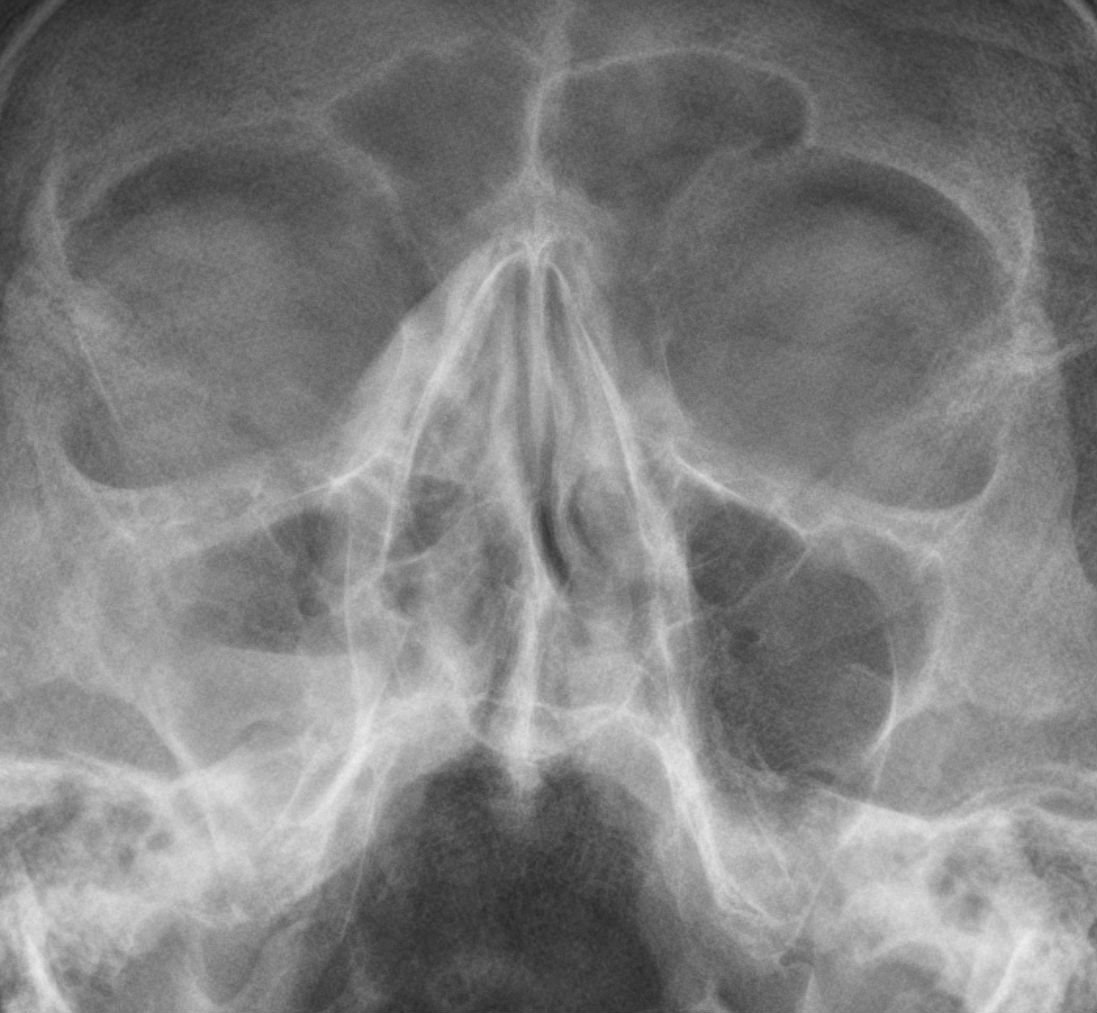

Rg ппн

Rg ппн 117 фото